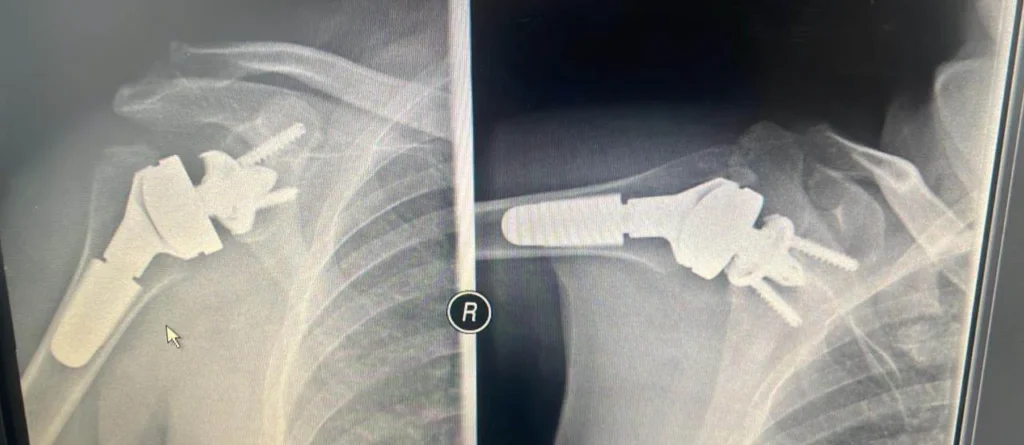

Τι συμβαίνει όταν κάθε κίνηση στον ώμο προκαλεί πόνο;

Ξεκίνησε σαν μια απλή ενόχληση. Οι πρώτες σκέψεις είναι πάντα οι ίδιες: ίσως να έγινε από κάποια απότομη κίνηση, μπορεί